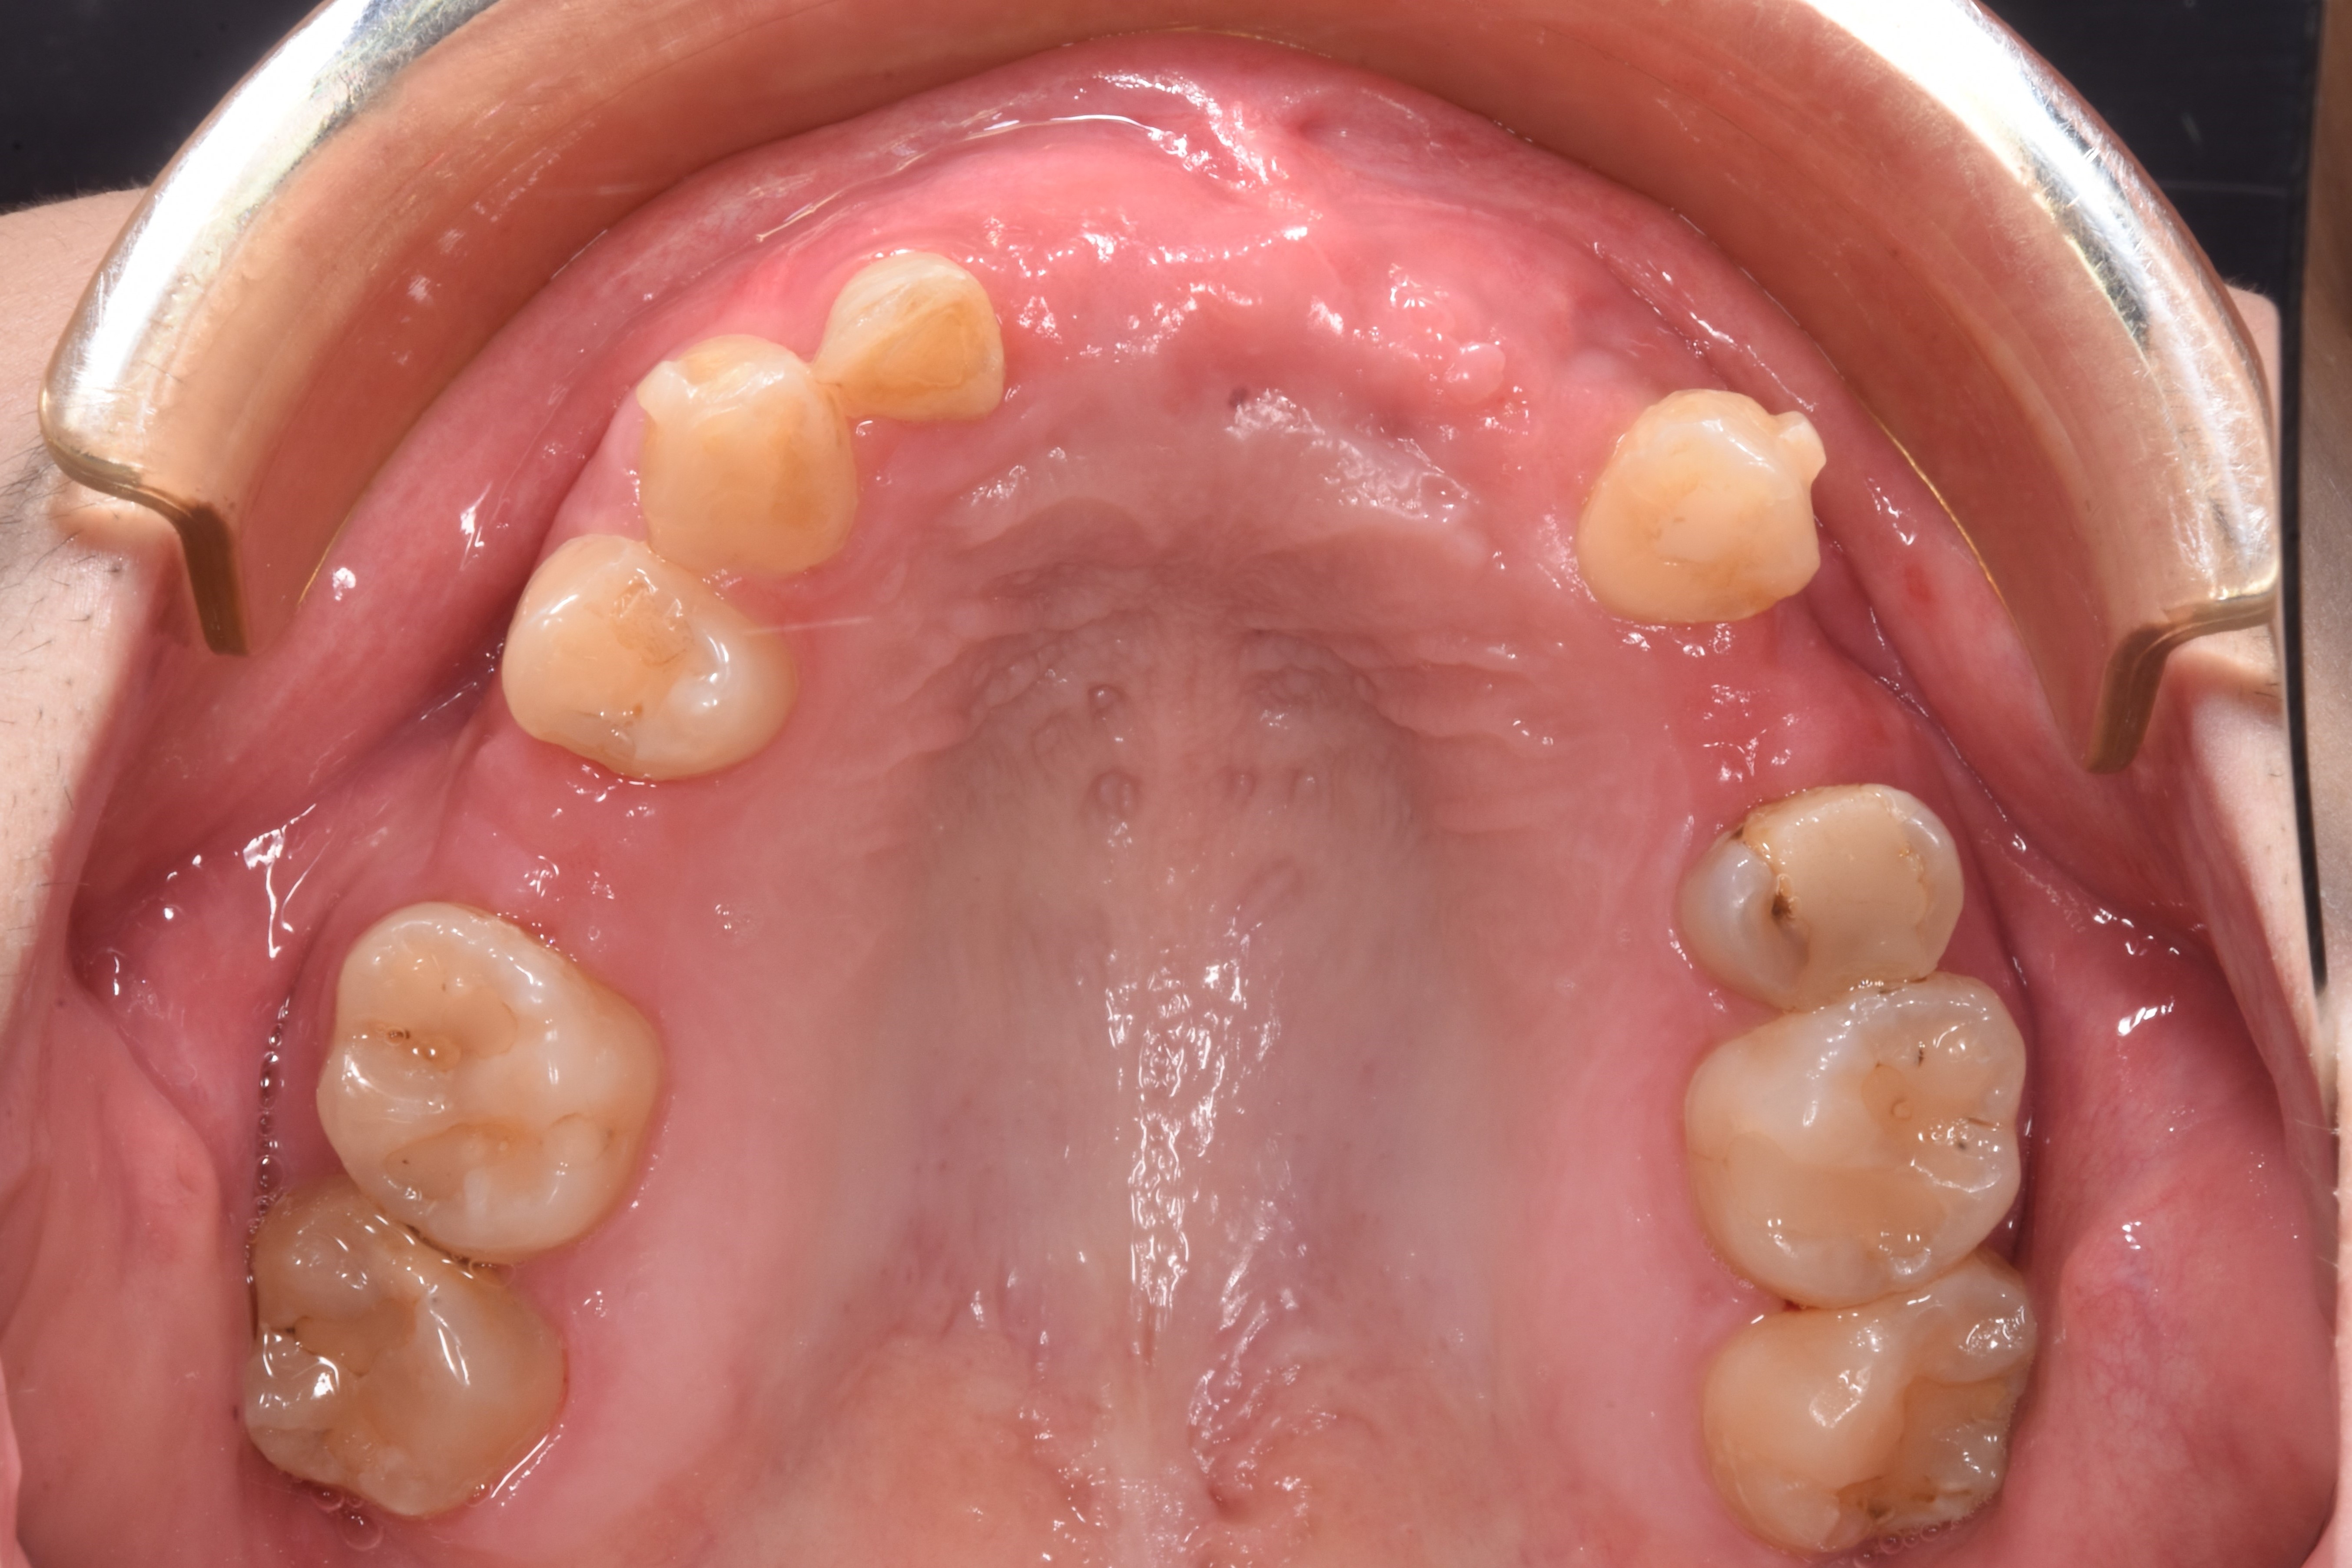

案例四

缺牙造成齒槽骨流失

翻瓣補骨的區域,先擷取所需不可吸收骨膜的大小,用骨釘固定

*不可吸收骨膜:不會被身體吸收、需要再開刀取出的膜,放在補骨區用來隔離軟組織並撐住空間,讓骨粉有足夠時間生長成新骨

補入所需骨粉

最後縫合傷口,等待癒合

完成後依骨頭恢復裝況,需定期回診給醫生評估是否進行下一個階段